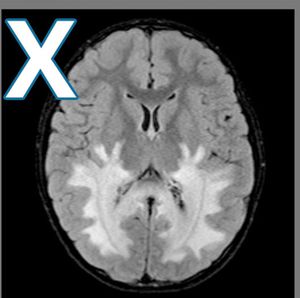

PRES or posterior reversible encephalopathy syndrome ?